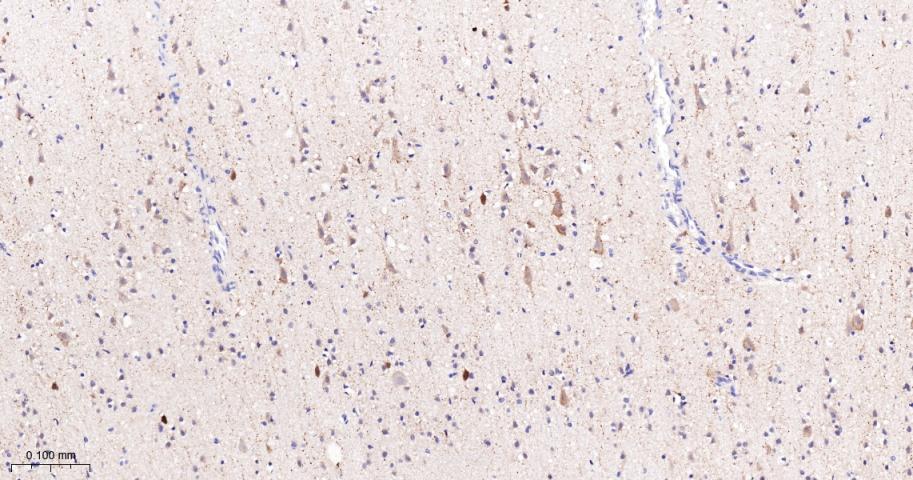

Paraformaldehyde-fixed, paraffin embedded Mouse Cerebrum; Antigen retrieval by boiling in sodium citrate buffer (pH6.0) for 15 min; The section was incubated with FDFT1 Monoclonal Antibody, Unconjugated (bsm-61816R) at 1:200 overnight at 4°C, followed by conjugation to the bs-0295G-HRP and DAB (C-0010) staining.